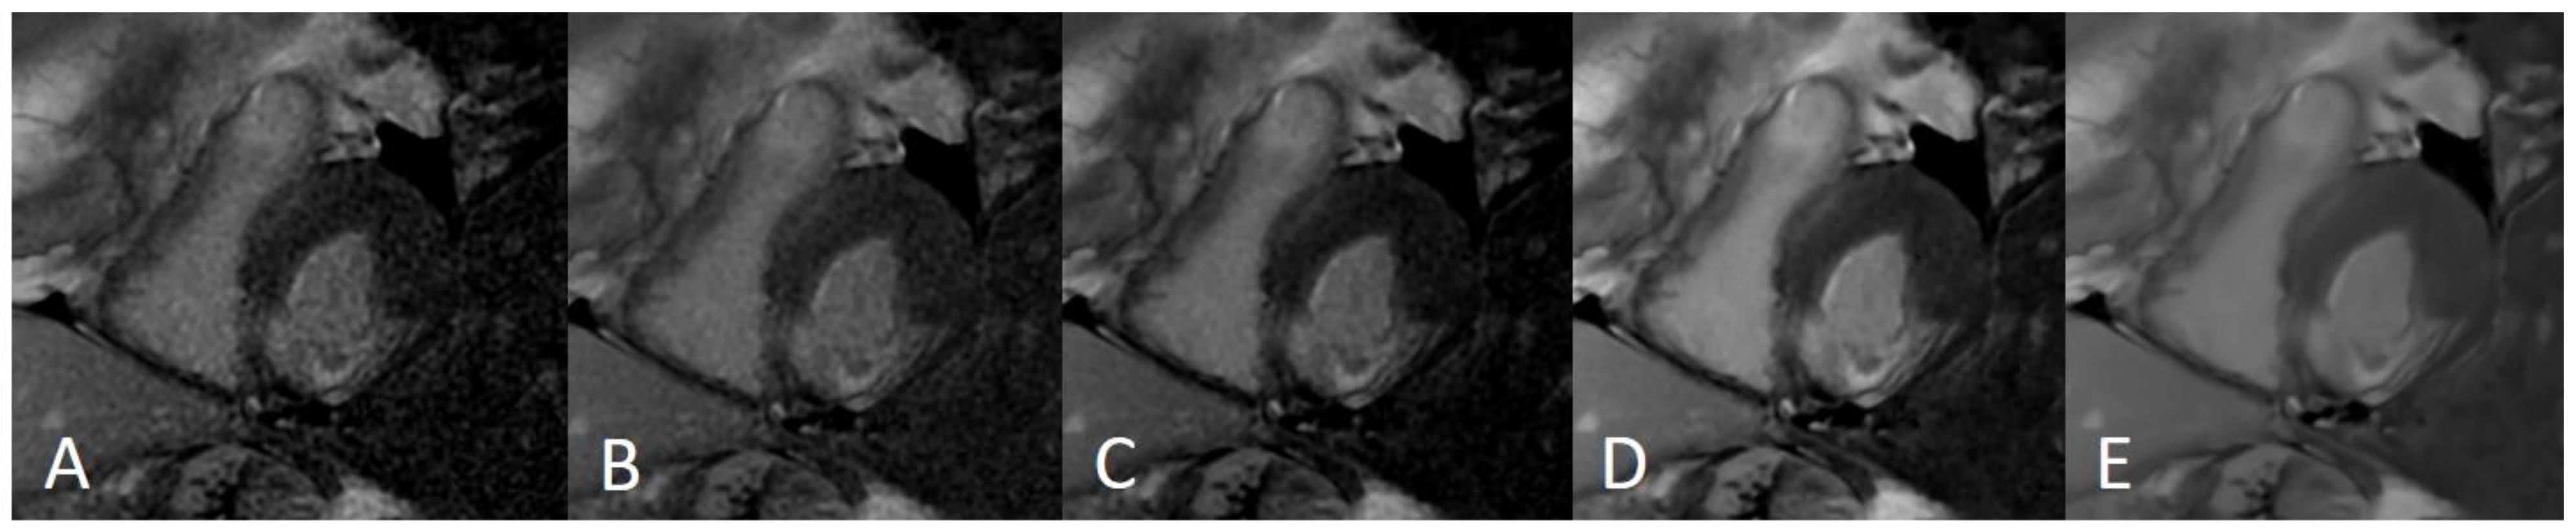

LGE sequences acquired using an artificial intelligence reconstruction deep learning algorithm. Forty-one-year old patient with previous myocardial infarction on anterior, anteroseptal, inferoseptal, inferior, and inferolateral segments (arrows, (A–E), respectively). Image noise decreased progressively with increase in AIRDL reconstruction in both 2D-SSLGE ((A): 2D-SSLGE AIRDL 0%, (B): 2D-SSLGE AIRDL 25%, (C): 2D-SSLGE AIRDL 50%, (D): 2D-SSLGE AIRDL 75%, (E): 2D-SSLGE AIRDL 100%). 2D-SSLGE—2D single segmented inversion recovery gradient echo late gadolinium enhancement sequences; AIRDL—artificial intelligence reconstruction deep learning.